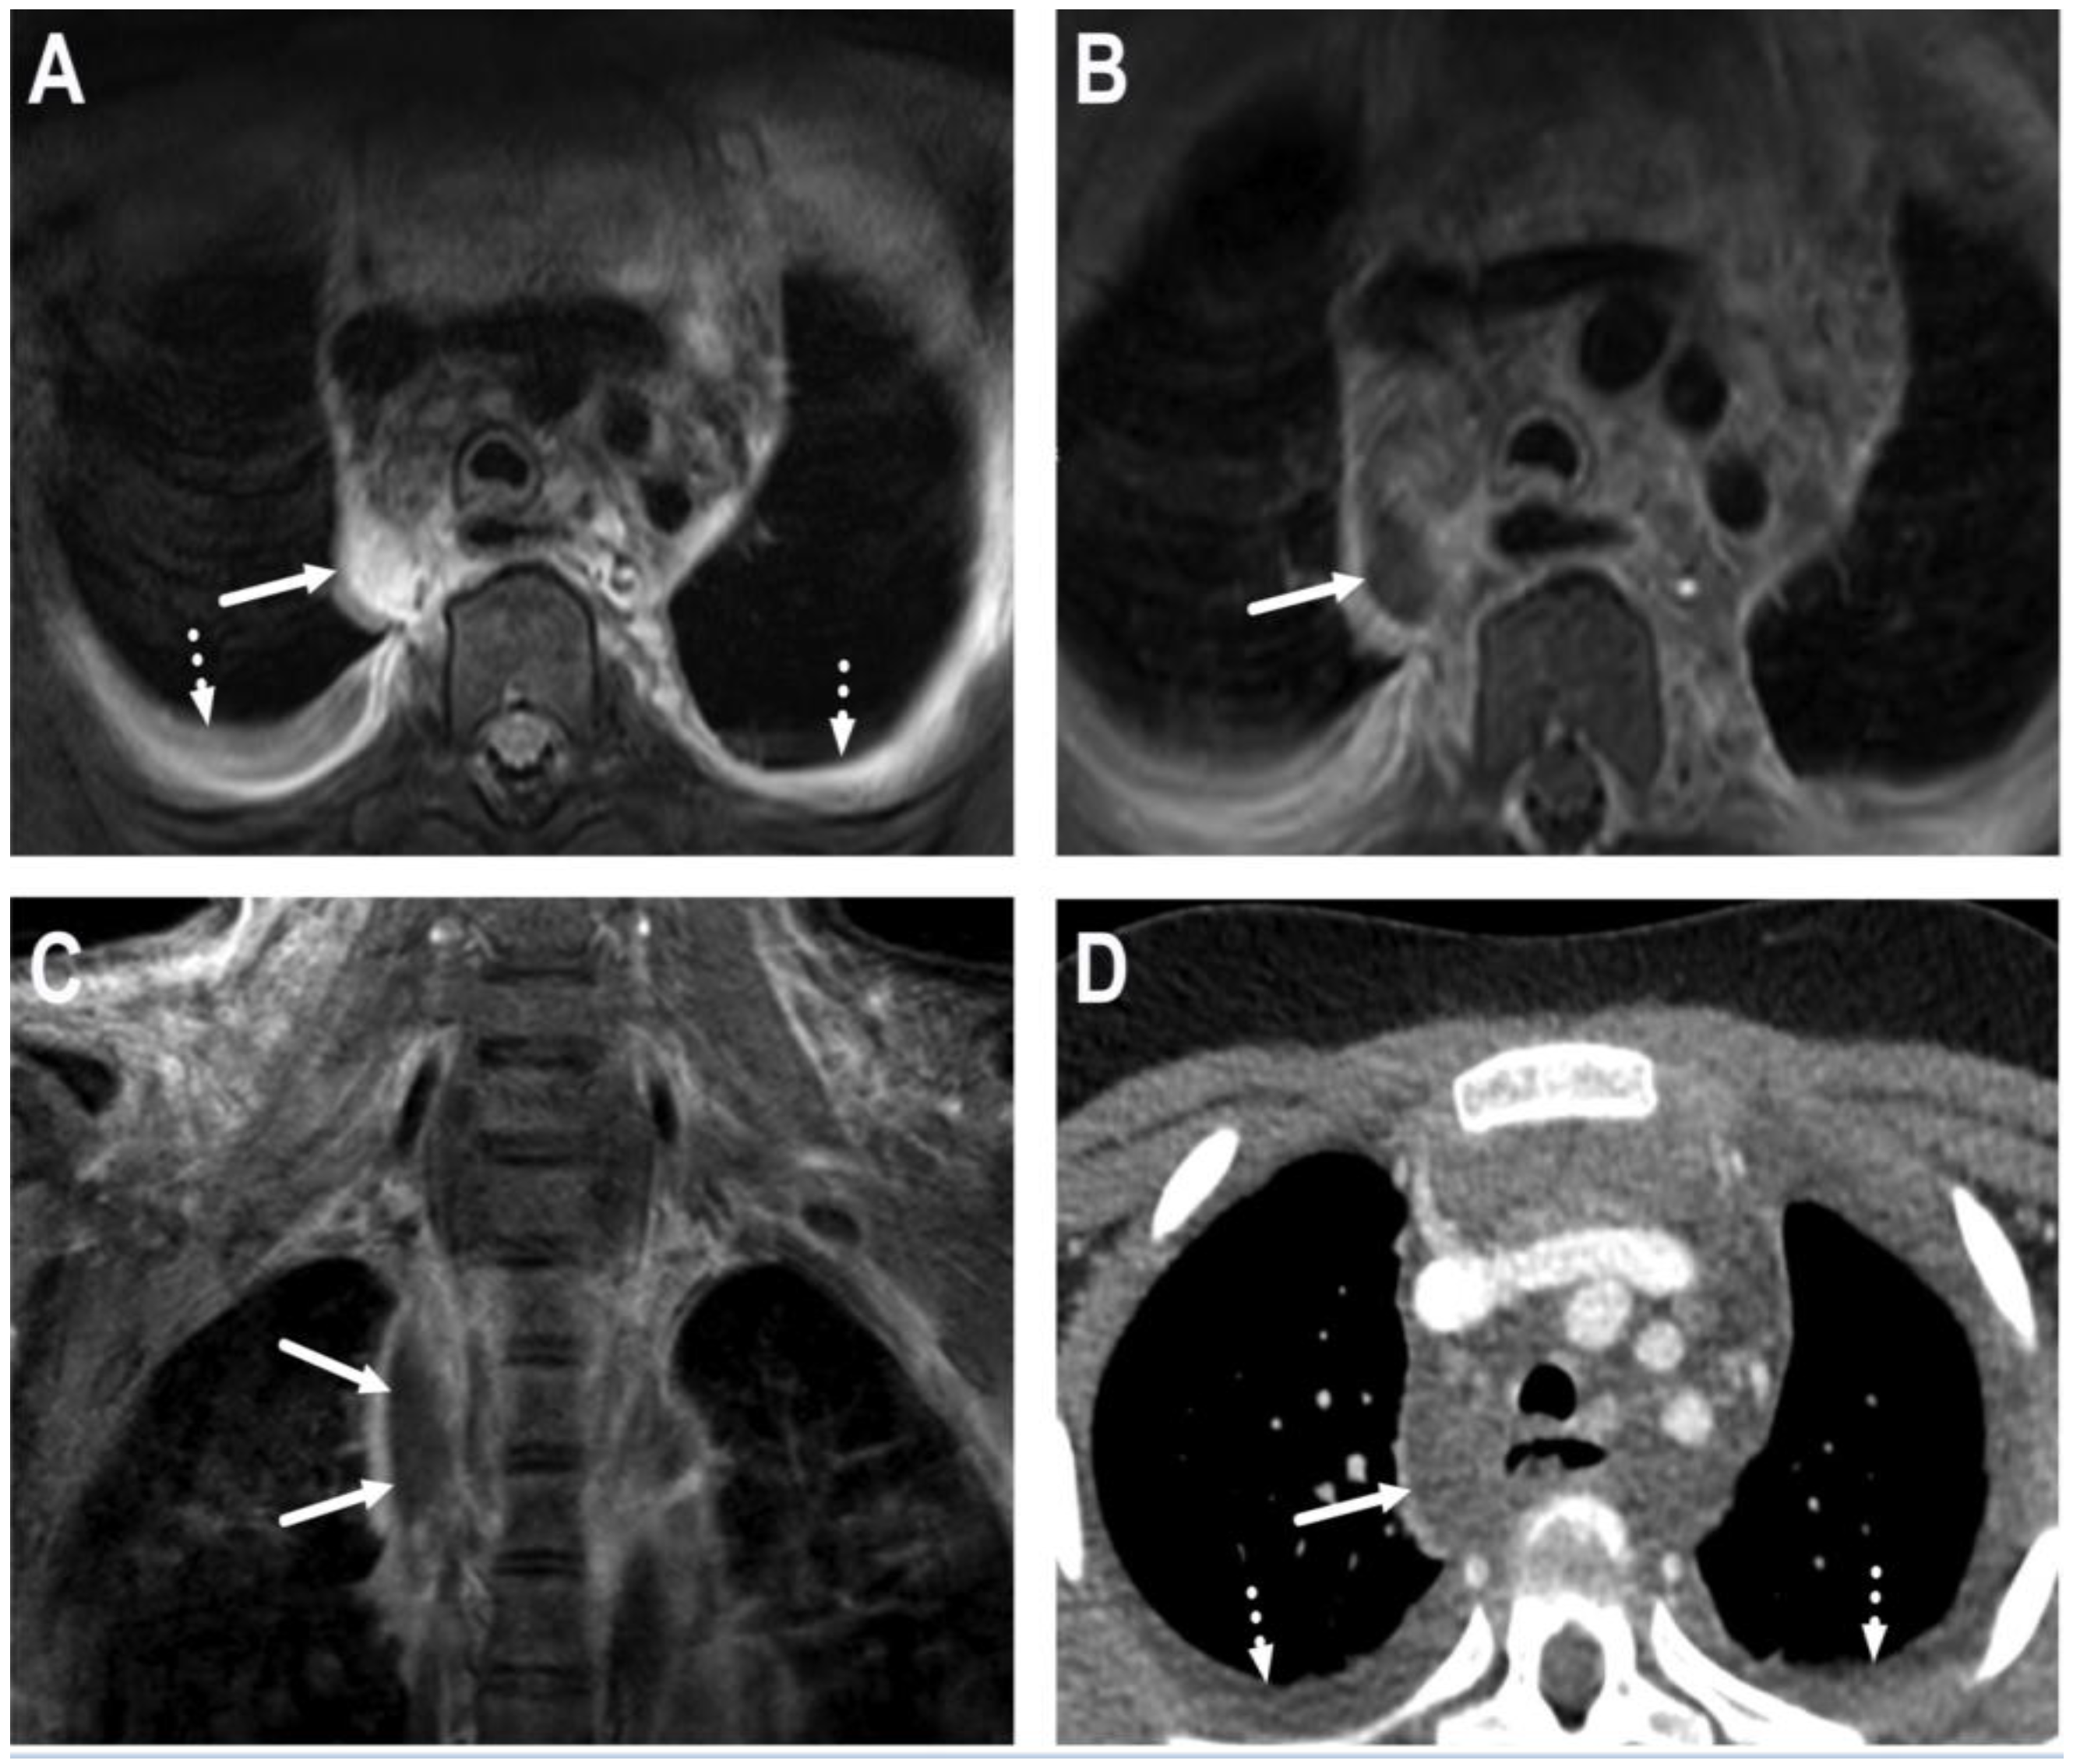

6. Complications

6.1. Mediastinitis

6.2. Venous Thrombosis